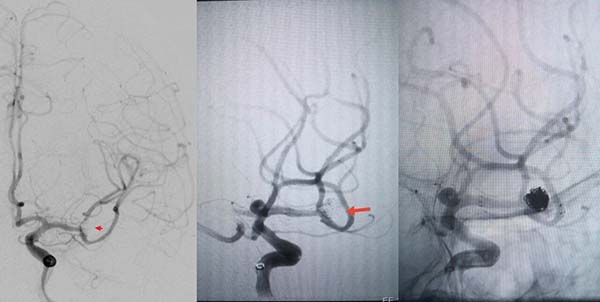

病例二为58岁女性患者。因“突发剧烈头痛伴呕吐3小时”就诊于清华大学附属垂杨柳医院急诊科,行头颅CT检查提示蛛网膜下腔出血。患者嗜睡,频繁呕吐,不排除颅内再出血。为争分夺秒抢救患者生命,神经外科脑血管病介入团队紧急为患者实施了DSA,显示左侧大脑中动脉分叉处宽颈动脉瘤,主要累及下干。术中采取双微导管技术,于动脉瘤内填塞弹簧圈,并置入一枚支架保证致密栓塞和下干分支血管的通畅。成功“拆弹”,化险为夷,患者恢复过程顺利,出院时无神经功能缺损。

▲术前DSA显示左侧大脑中动脉分叉

宽颈动脉瘤可见子瘤,主要累及下干

▲术后DSA显示动脉瘤致密栓塞,载瘤动脉通畅